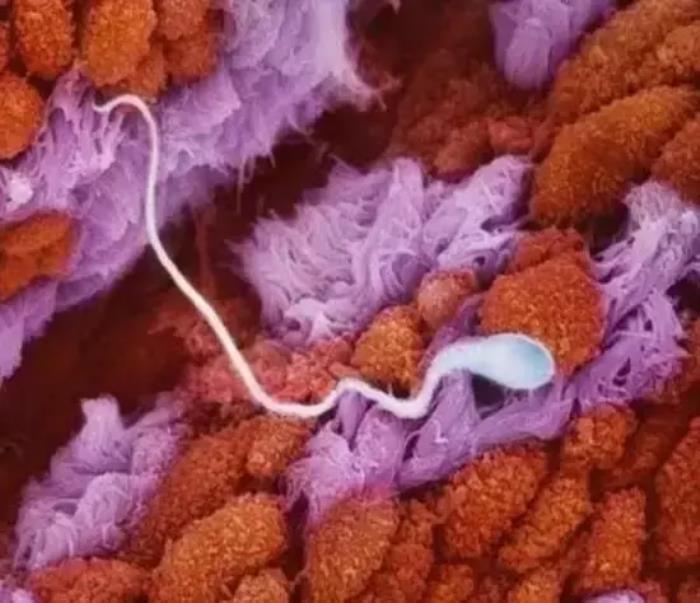

精子在输卵管里游动

2亿精子中只有一颗精子与卵子结合

一个精子的纵切面,遗传物质储存在精子头部